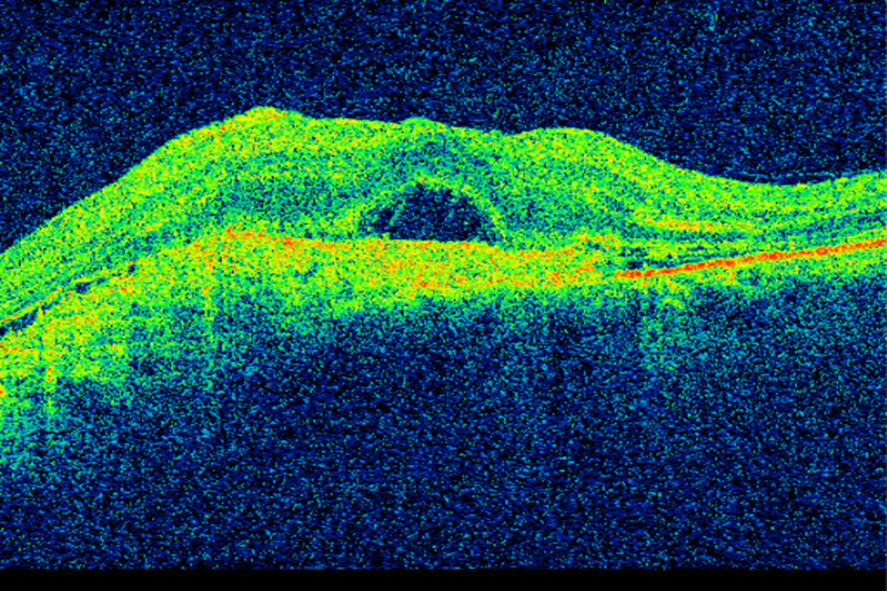

Figure 2 OCT of the macula in a patient with wet age-related macular degeneration prior to initiation of anti-VEGF treatment…

Figure 2 OCT of the macula in a patient with wet age-related macular degeneration prior to initiation of anti-VEGF treatment. Retinal thickening and subretinal fluid can be seen. Visual acuity is 0.1.